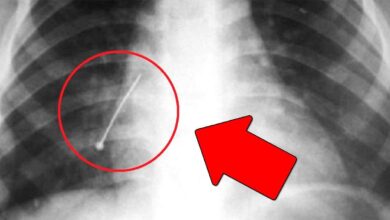

Мальчик 2 дня ходил с иголкой внутри

Врачи Карагандинской области извлекли иголку из живота 10-летнего мальчика, который два дня ходил с этим опасным предметом в организме, передает…